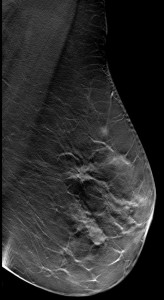

Caso 04

María Esther Estornell Cánovas